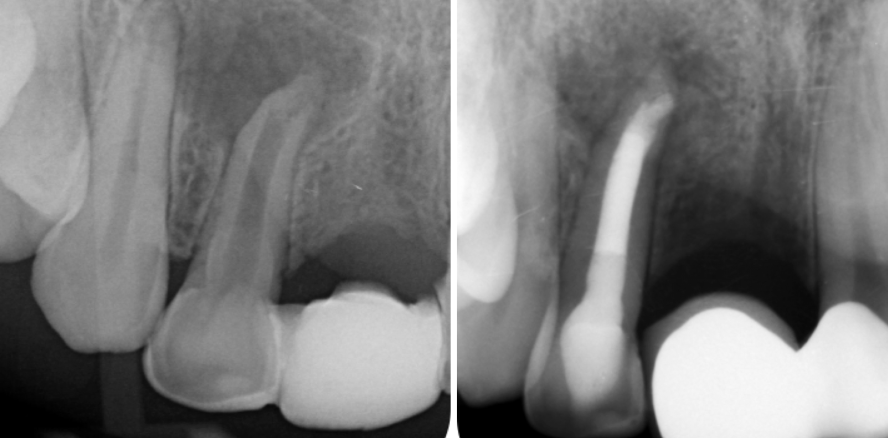

Apikale Läsionen mit ausgeprägter Ausdehnung stellen in der endodontischen Behandlung eine besondere Herausforderung dar. Radiologisch sichtbare...

Apikale Läsionen mit ausgeprägter Ausdehnung stellen in der endodontischen Behandlung eine...

Bereits wurzelkanalbehandelte Zähne mit persistierenden apikalen Parodontitiden oder Osteolysen werden trotz großer Fortschritte in der Endodontologie...

Bereits wurzelkanalbehandelte Zähne mit persistierenden apikalen Parodontitiden oder Osteolysen...